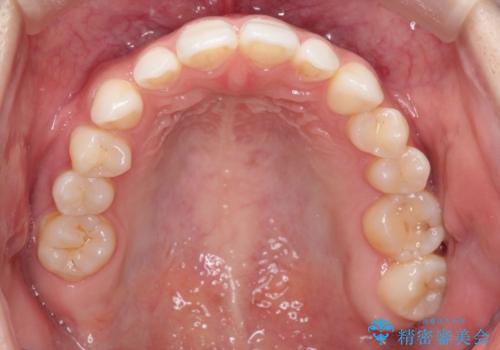

- 空隙歯列を主訴に来院された患者様です。

ばらけている空隙を一箇所に集めながら咬合や正中を改善して最後に補綴治療を行なっています。

右上の臼歯クロスバイトは骨格生のため、そのままにしています。